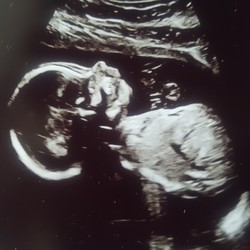

Met de termijn echo van 12 weken bleek een iets verdikte nekplooi waardoor we niet in aanmerking kwamen voor de NIPT.

Vandaag te horen gekregen dat het een jongetje is (hadden middels mijn bloed het geslacht bepaald, in de hoop zo de vlokkentest te vermijden)

Nu dus a.s. maandag alsnog een vlokkentest, enig idee of de uitslagen vanuit DNA of chromosoom onderzoek? Ze vertelde mij namelijk tussen de 2 en 3 weken te moeten wachten op de uitslag, duurt zo lang voor mijn gevoel!